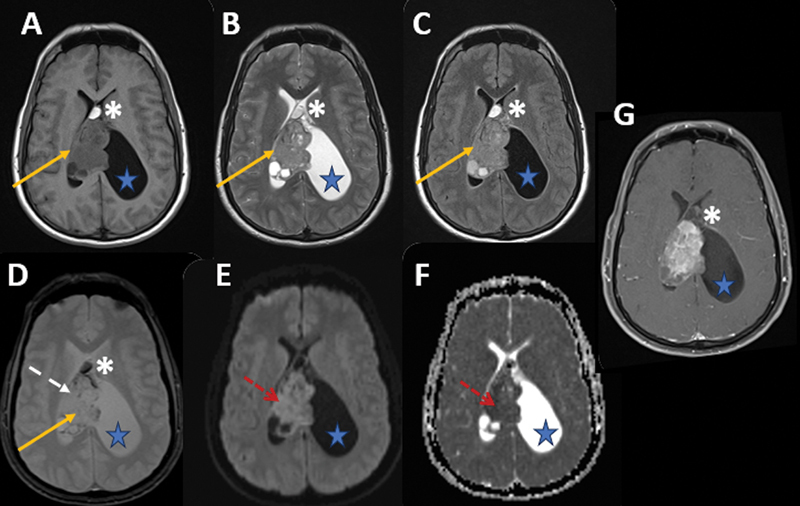

Lateral ventricle central neurocytoma with lipidization: a case report of an underrecognized presentation.

侧脑室中枢神经细胞瘤伴脂化:一例未被充分认识的表现。